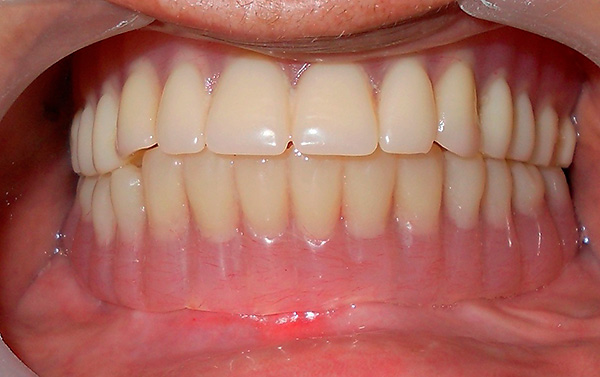

Em terceiro lugar, a prótese permite que o paciente se sinta pleno - a estética e a possibilidade de nutrição são restauradas com implante basal quase que imediatamente.

No entanto, há um ponto muito importante (que alguns podem considerar um sinal de menos). Embora após a instalação dos implantes a prótese seja fixa permanente, não removível, mas ainda assim seja uma estrutura temporária. Isso significa que você precisa usá-lo por pelo menos seis meses e, na prática - até 3-4 anos, até as coroas plásticas falharem e perderem a aparência. Após a prótese, você terá que substituí-la por uma permanente - ou seja, uma que permaneceu inativa por décadas.

Com atrofia significativa do tecido ósseo, é oferecida aos pacientes uma prótese fixa, cujas coroas são presas a uma base de acrílico ou usando material Acry Free - um tipo de goma artificial. É pequeno, pouco perceptível e praticamente não se sente na boca. Esse sistema permite ocultar o contorno irregular da mucosa natural, que afunda junto com o osso.

Se você colocar uma ponte feita apenas de coroas, elas serão excessivamente longas. Nesse caso, os médicos ainda usam um termo especial - "sorriso de cavalo".

As pontes dentárias de metal cerâmico (veja o exemplo na foto abaixo) terão uma duração média de 10 a 12 anos.

Enquanto isso, uma das mais confiáveis e estéticas é considerada uma coroa de zircônia com uma vida útil de mais de 20 anos (mas também pelo preço de fabricação, essas coroas serão muito mais caras que as de cerâmica-metal).